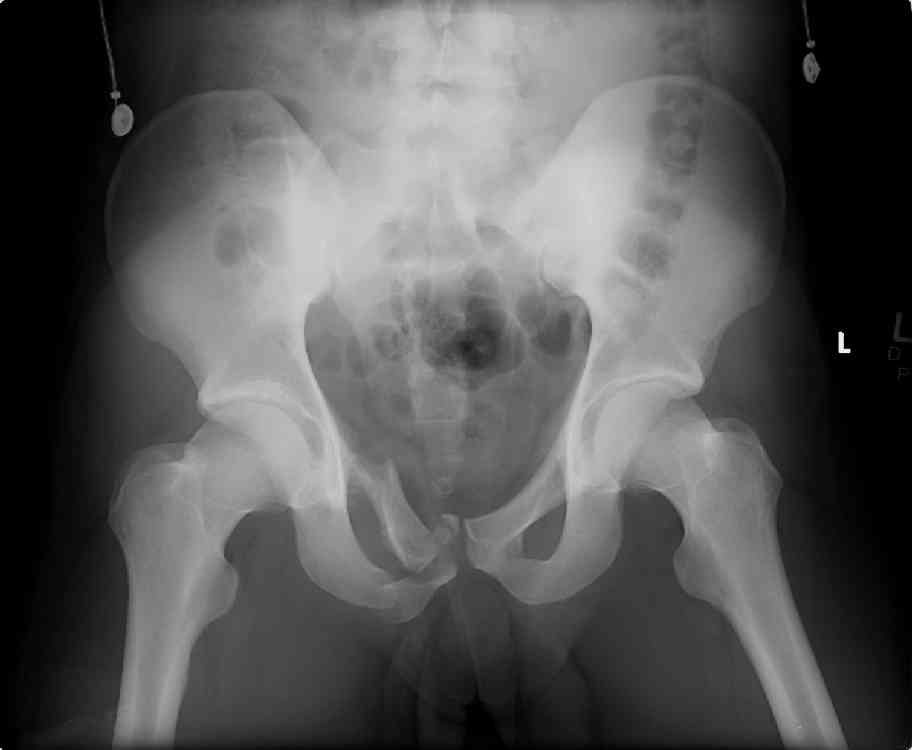

hello, this is a healthy 22yo male. peds vs auto.

no other injuries. has anyone treated these non-operatively? thanks.

dan